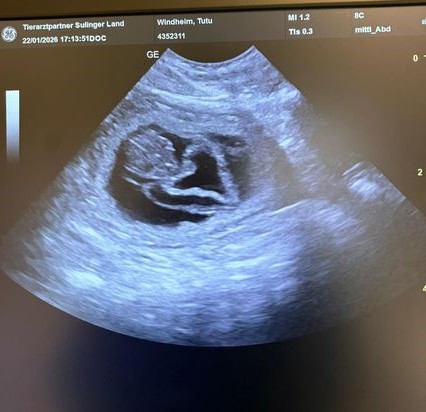

Heute haben die Auswertung von Hetties HD-Röntgen bekommen. Die Ergebnisse sind nahezu perfekt:

HD A2    ED 0    OCD bds.frei  LÜW 1

Wir freuen uns sehr, damit stünde einer möglichen zukünftigen Zuchtverwendung von Hettie nichts im Wege.